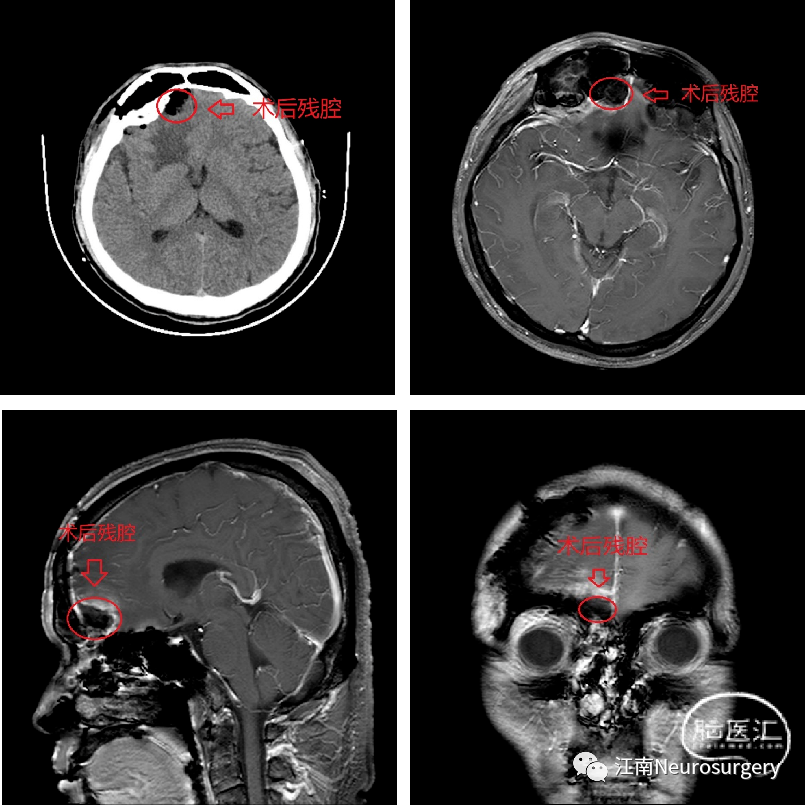

入院后完善检查,查颅脑平扫+颅脑增强+头MRA(TOF)+头CE-MRA(3.0T)提示(图1):右侧额叶占位伴水肿,邻近白质纤维束受压中断,考虑:不典型脑膜瘤。患者颅内占位诊断明确,周围占位压迫所致水肿效应明显,于2022-10-24日全麻下行“额下入路脑病损切除术”。患者气管插管全身麻醉后,仰卧位,头抬高,常规消毒铺巾单。切开皮肤,皮下组织,帽状腱膜,游离皮瓣。剥离骨膜。钻孔,铣刀切开骨瓣,悬吊硬膜,见右侧额窦开放,予碘伏交替双氧水冲洗两次,去除额窦黏膜,予骨蜡封闭窦腔,四周悬吊硬膜止血,人字型剪开硬膜,见额部皮层张力较高,予右侧经外侧裂打开蛛网膜下腔释放脑脊液,见额叶明显塌陷,上抬额叶,中线旁右侧嗅沟区见质韧灰白色肿块,肿瘤大小约4*3.5*4.5cm,分离肿瘤和周围脑组织的界面,保护好周围的动脉和静脉。电凝肿瘤表面,使肿瘤缩小(图2A);沿肿瘤与正常脑组织界面分离(图2B);分块切除肿瘤,使肿瘤体积缩小(图2C);进一步释放脑脊液,使脑组织塌陷,创造更大的手术空间(图2D);在分离的肿瘤-脑组织界面填入明胶分隔(图2E);电凝肿瘤表面使其进一步缩小(图2F);铲除肿瘤基底(图2G);肿瘤切除后所剩残腔,无出血(图2H)。瘤腔充分止血后,止血纱覆盖瘤腔,流体明胶填塞,采用部分肌肉筋膜代替硬膜,水密缝合硬膜,骨瓣回纳,采用bioplate连接片3套固定。皮下仔细止血,逐层缝合肌肉及帽状腱膜,予倒刺线皮内缝合头皮。术后复查MRI见肿瘤切除满意,未见明显残留(图3)。术后病理结果提示:右侧额叶脑膜瘤,肿瘤组织呈侵袭性生长,部分区域细胞丰富,有异型,核分裂像可见(图4)。患者手术恢复良好,顺利出院。

图3. 术后复查头颅CT及MRI,未见明显残留。